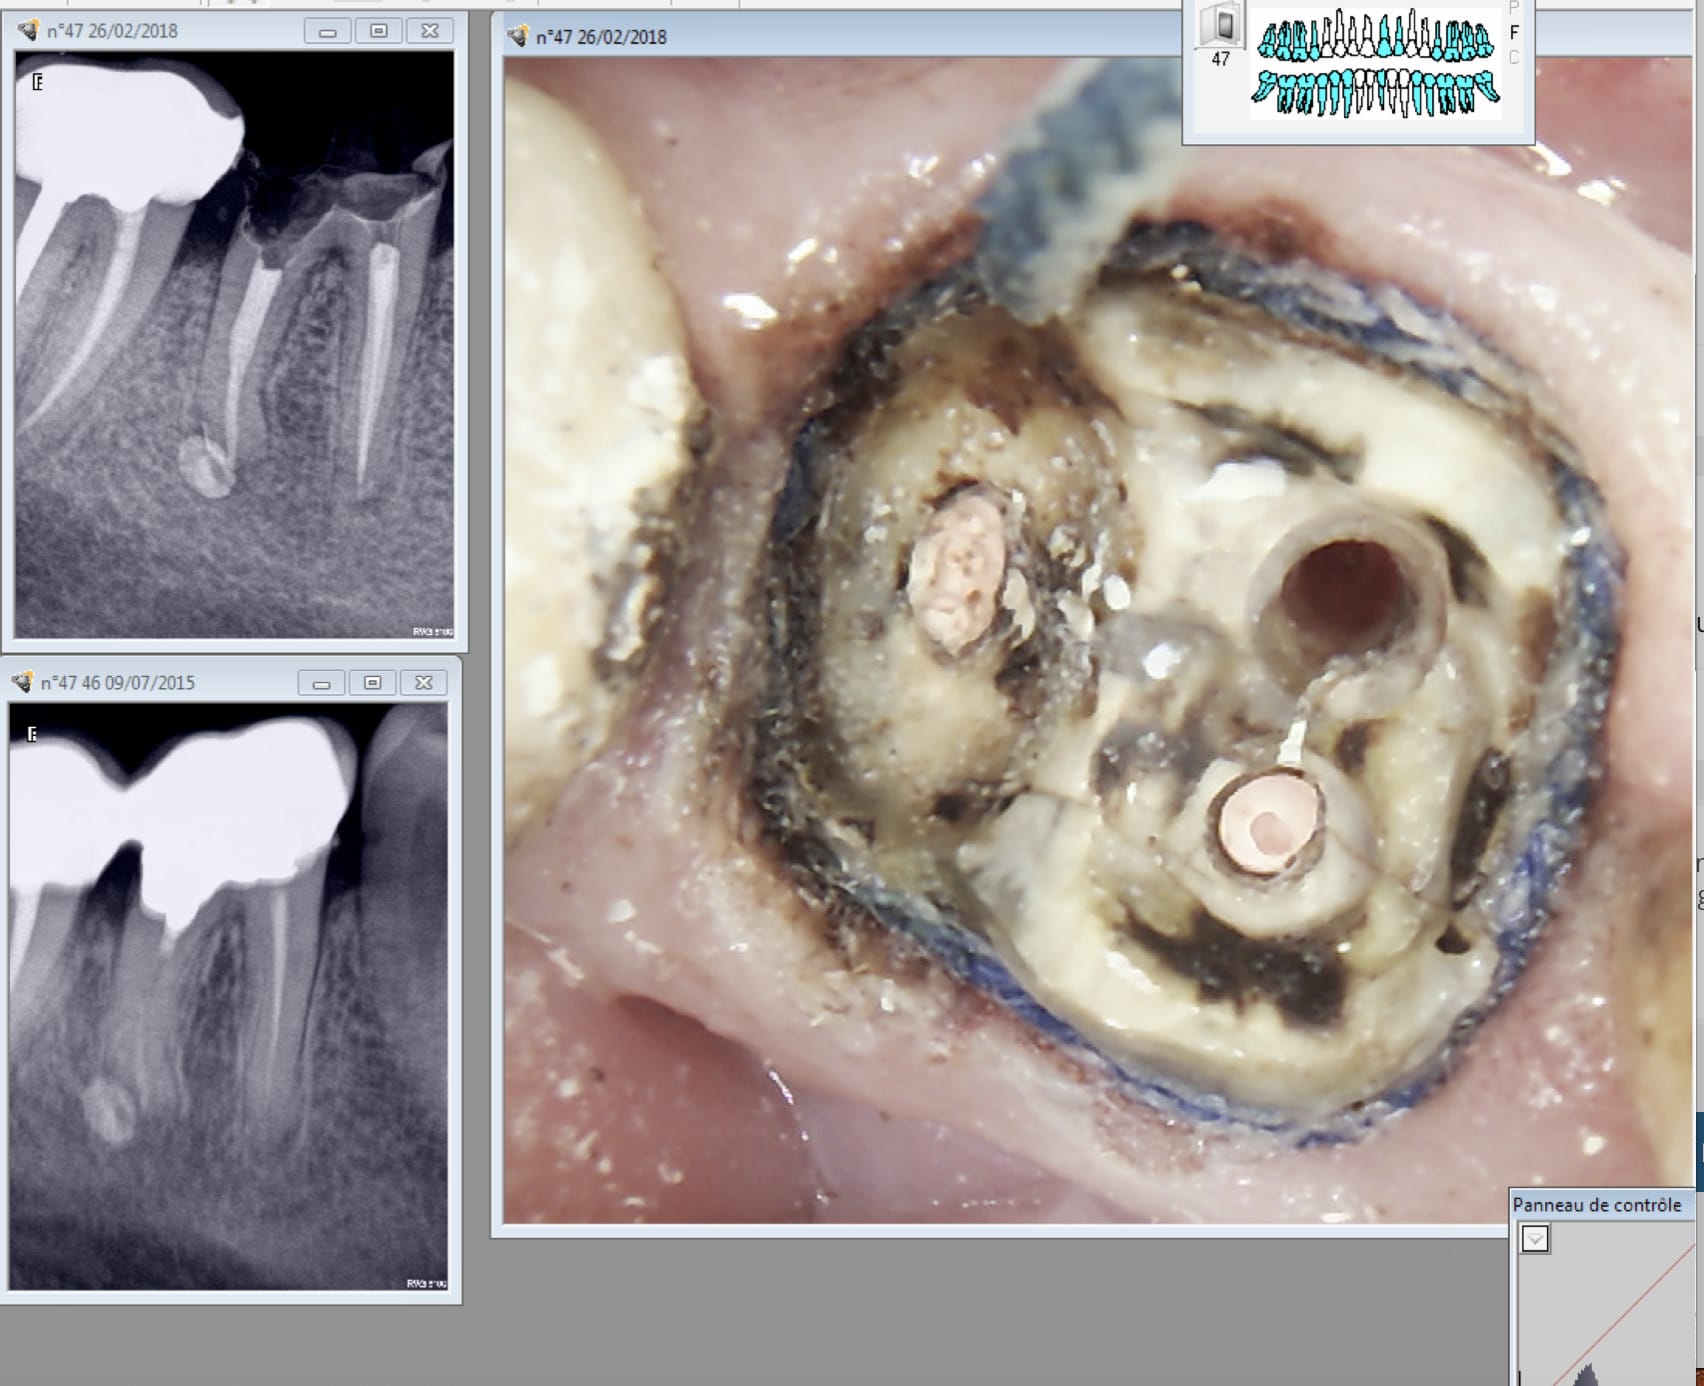

L'autre est pas Top. Trop pressé de faire l'empreinte et toute mon attention a été captée pour trouver les limites en distal. 4 mm sous gingival. Après un . RTE sportif + dépose couronne soudée ( j'ai re scellé la 47)

Là tu te dis ca va saigner ! -))) Donc tu recrées un sillon gingival au laser + double fil.

Première empreinte......

Tiens ? Un micro trou dans le composite du moignon. Je l'avais pas vu meme avec des loupes. -))))